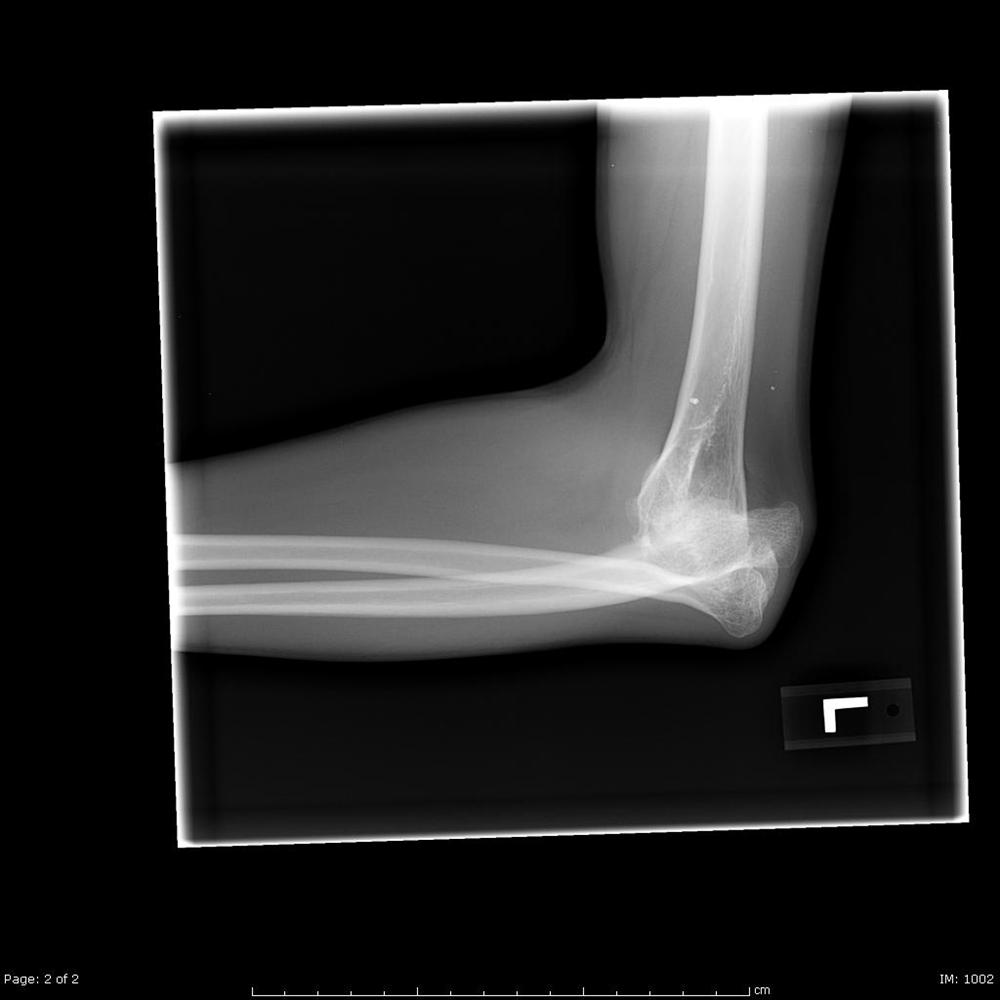

Posterior Elbow Dislocation, Oblique XRay, dislocated, Annotated. JETem Type Of Elbow Dislocation 90% of elbow dislocations occur posteriorly, with 50% suffering bony injury. Dislocations may be isolated, involve damage to. When the joint surfaces of the elbow's three bones are separated, the elbow is dislocated. The elbow is the second most common dislocation in adults. The two general types of elbow dislocation are: An elbow dislocation is defined as simple or complex*,. Type Of Elbow Dislocation.

Posterior elbow dislocation Image Type Of Elbow Dislocation An elbow dislocation is defined as simple or complex*, the latter being associated with a concomitant fracture. 90% of elbow dislocations occur posteriorly, with 50% suffering bony injury. The elbow is among the most common large joints to dislocate. Dislocations may be isolated, involve damage to. Elbow dislocations usually occur in the young adults and account for up to 25%. Type Of Elbow Dislocation.